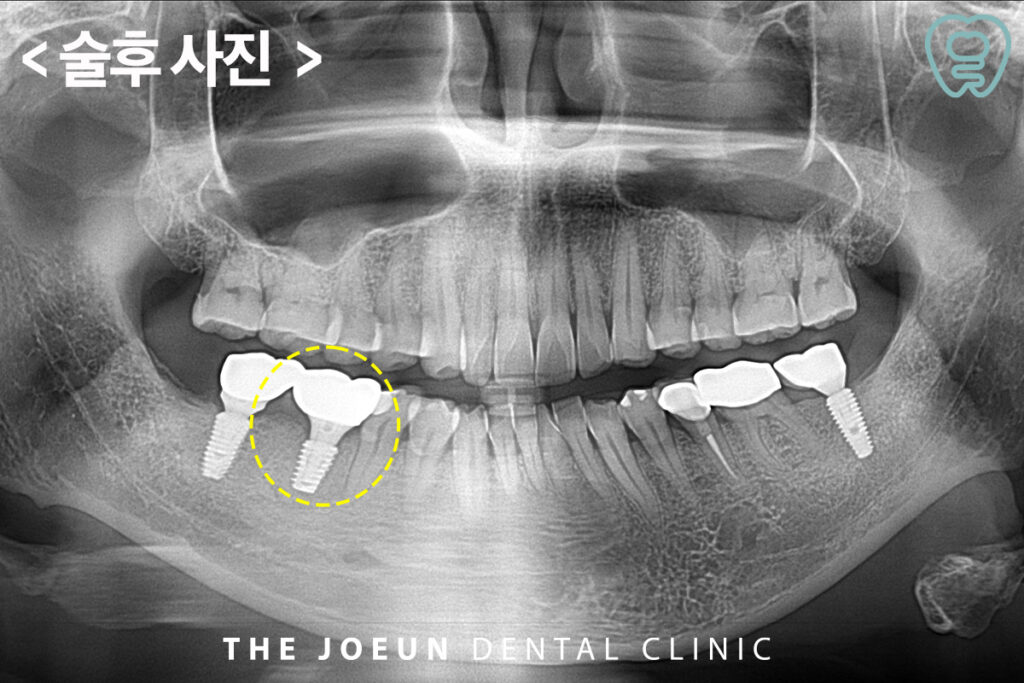

6개월 뒤 임플란트 식립을 진행하였습니다. 임플란트는 치조골에 인공 치근을 식립하는 방식이므로 골조직이 튼튼해야만 안정적으로 고정이 되는 것이 기본으로 성공의 핵심은 골유착에 있다고 해도 과언이 아닌데요. 골유착이란 뼈와 임플란트가 단단히 결합해 씹는 기능을 무리 없이 수행할 수 있을 만큼 안정적으로 고정되는 상태를 말합니다. 골유착이 제대로 이루어져야 임플란트의 수명이 길어지고 일상 속 불편함도 줄일 수 있습니다.

이어서 최종 보철물까지 마무리를 하였습니다.